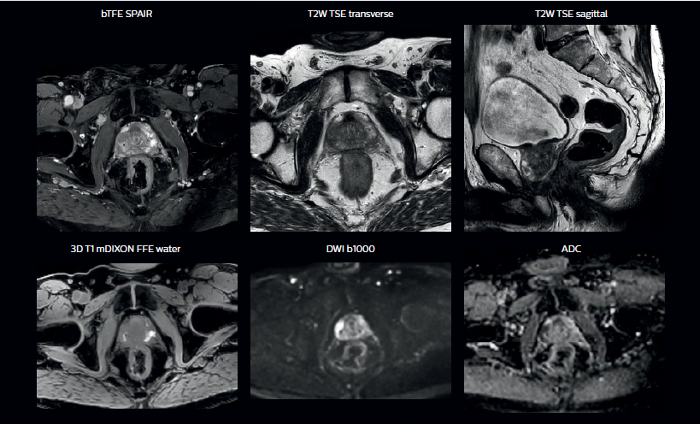

In addition to anatomical imaging, MRI offers the ability to obtain functional information that is beneficial for tumor detection and delineation, and for response monitoring.

Diffusion-weighted imaging (DWI) for example depicts areas of high signal intensity in soft tissues that are indicative of the restricted water mobility (i.e., diffusion) of a tumor and can also be used to identify lymph nodes. Changes in the tissue’s or lesion’s apparent diffusion coefficient (ADC) can provide insights that help predict the tumor’s response to radiotherapy.